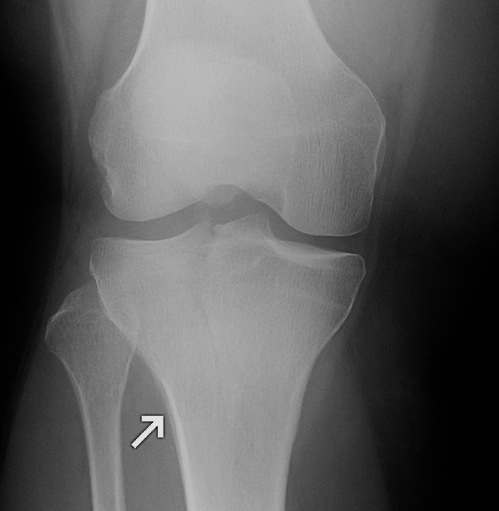

Xray

- sclerotic and overgrown